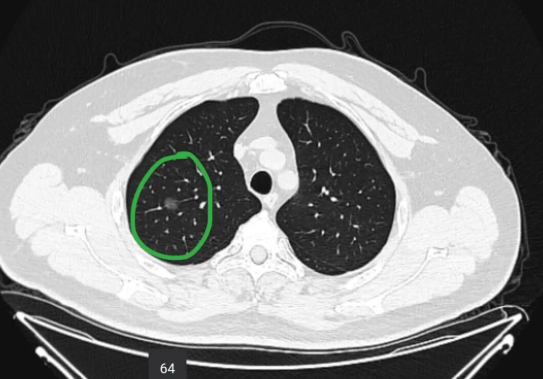

肺結(jié)節(jié)CT影像

以肺結(jié)節(jié)來說,絕大多數(shù)人得了肺部結(jié)節(jié)是沒有感覺的,既不咳嗽也不胸痛,直到做肺部CT體檢時才發(fā)現(xiàn),甚至因發(fā)現(xiàn)得晚,有部分肺結(jié)節(jié)或面臨癌變的風(fēng)險。